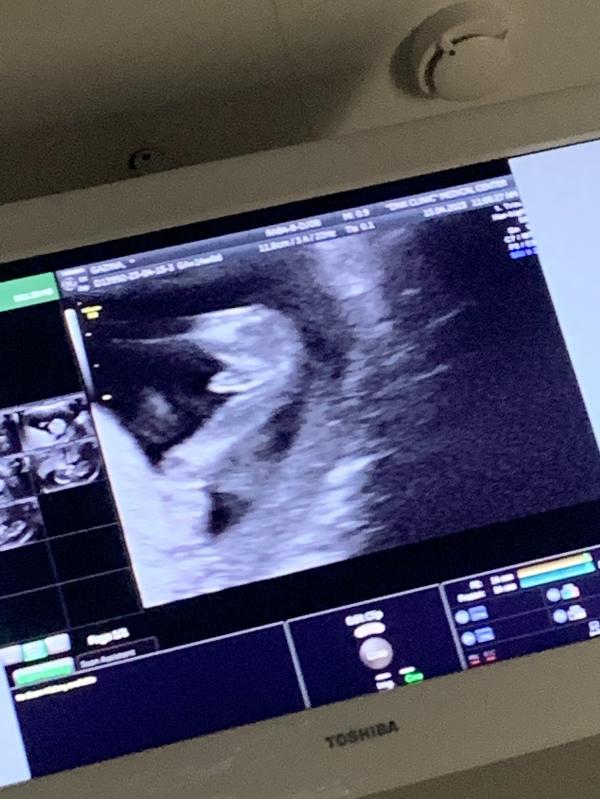

Сходила я все таки перепроверить 1 скрининг в платную поликлинику 😀

Всё хорошо 👌 как и должно быть, пол даже не спрашивала , нам малыш решил сам показать своё добро😄. И вот в 14 недель мы знаем кто у нас будет))